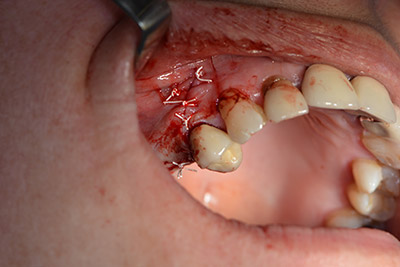

Una membrana reabsorbible formó la barrera en sentido bucal y cubrió el aumento. Por último se procedió a la sutura de modo que no penetrara saliva (figuras 15 a 19).

Aumento con hueso autógeno

Imagen 15

Imagen 16

Implantología

Imagen 17

Imagen 18

cierre de la herida para que no penetre saliva

Imagen 19